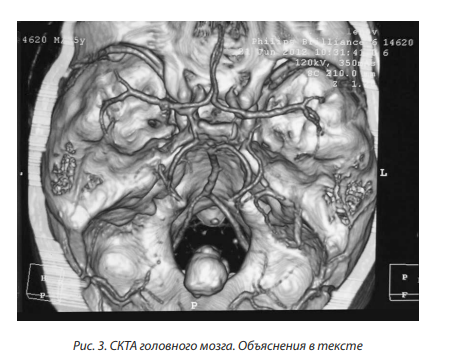

СКТА выявила вариант строения Виллизиева круга (круг разомкнут в области обеих задних соединительных артерий (ЗСА), левая ЗМА отходит от внутренней сонной артерии); наиболее вероятно имеет место обызвествленная кавернома червя мозжечка (рис. 3).